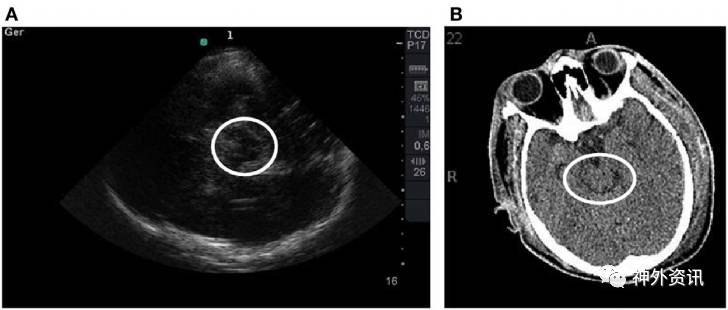

该研究共纳入15例患者,TCCS均在颅脑CT扫描前6h完成。比较患者进入ICU后的第1次CT扫描与TCCS结果。通过Bland-Altman法和评估组内相关系数(>0.75认为相关性强)分析二者一致性。15例患者中男性占80%,平均年龄为42±23岁,GCS评分为5。测量中线偏移,颅脑CT与TCCS结果的平均差异为0.30±2.1mm(组内相关系数:0.93,p<0.01)。第三脑室宽度测量,二者同样表现出极强相关性(0.88,p<0.01)。一致性分析显示,Bland-Altman法未表现出系统偏差。同时,与颅脑CT扫描相比,TCCS对判别非受压所致的中脑周围池和大脑外侧裂改变的精确度较高(图1、2)。

图1. A图中TCCS的白圈内中脑平面蝴蝶翼样结构,与B图中CT扫描结果相对应。